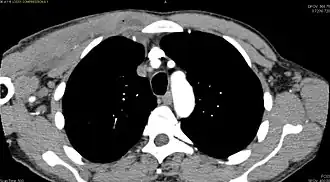

Additional images

-

CT with IV contrast showing enlargement and heterogeneous hypodensity in the right pectoralis major muscle. A focal abscess collection with gas within it is present medially. There are enlarged axillary lymph nodes and some extension into the right hemithorax. Note the soft tissue and phlegmon surrounding the right internal mammary artery and vein. The patient was HIV+ and the pyomyositis is believed to be due to direct inoculation of the muscle related to parenteral drug abuse. The patient admitted to being a "pocket shooter" -